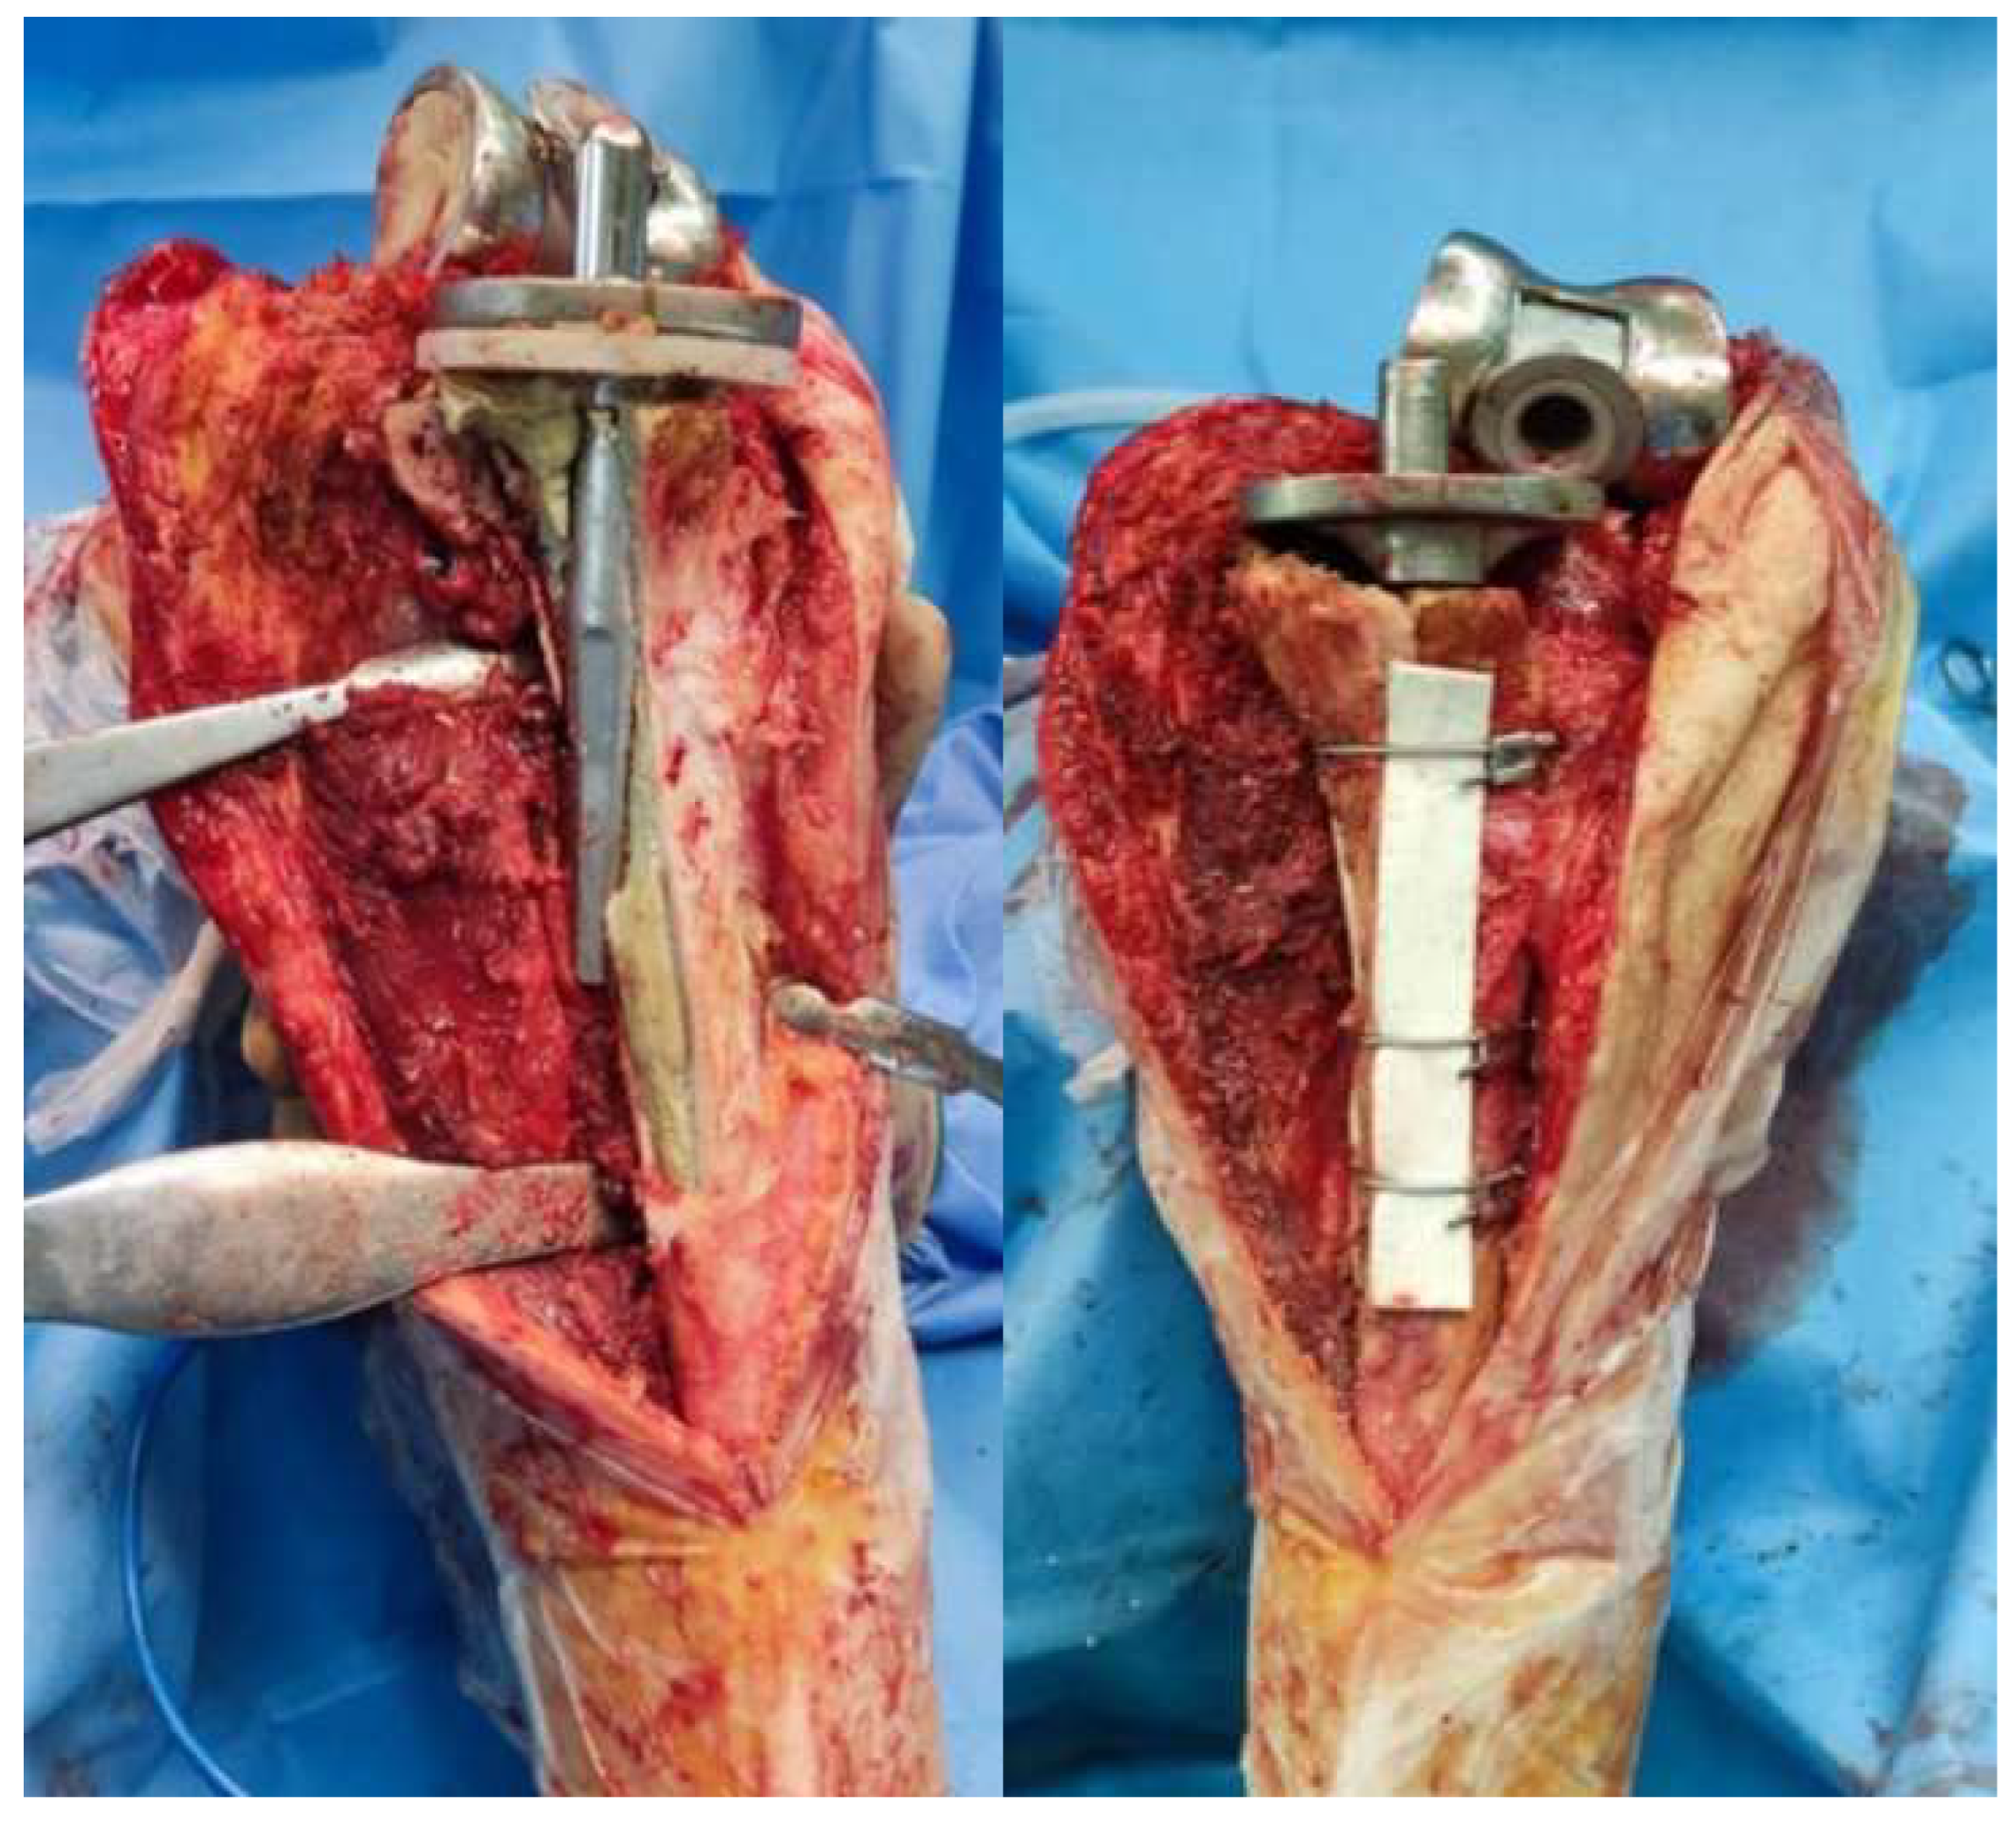

Preparation of the intramedullary canal followed, and trial implants were then tested. The final implants were considered as “hybrid”, since the metaphyseal part was fixed with cement, whereas the stem was uncemented. In cases where tibial reconstruction was needed because of the osteotomy, we typically proceeded with the implantation in two (2) stages, one for the femoral component and one for the tibial one. For the tibia (second stage), the bone fragment was reduced manually with the final tibial implant in place and the knee in a 90-degree flexion. Usually, there was no need for reduction forceps to obtain reduction. One should be very cautious when reduction forceps are used, to avoid fragmentation of the bone flap as it is very thin and fragile. Obtaining a near-anatomic reduction was crucial for osteotomy union. Three wire cerclages were passed to stabilize the bone fragment using a cerclage wire passer (Figure 2). The distance between them depended on the osteotomy length. The wires were tightened sequentially on the medial side of the tibia, starting from the most distal and proceeding to the most proximal.

Figure 2. Cerclage wires reducing the bone flap with the final tibia implant in place. Note the length and transverse cut of the osteotomy (Case 3).

Figure 3. Final construct with three cerclage wires and final implants. Cement excess is removed from the osteotomy site (Case 3).